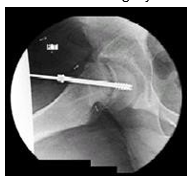

- A pin is put into the femur at the hip (see photo to the right). This will hold the slipped epiphysis on the femur to keep it from slipping any more. X-rays are used during the surgery to help the surgeon see where to put the pins.